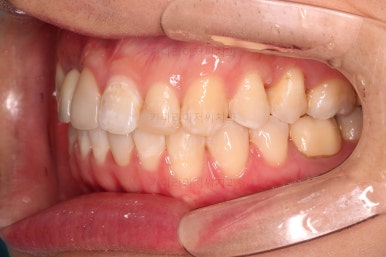

초진 시 입안의 모습입니다.

화살표는 결손 부위, 동그라기믄 유치잔존과 매복치아 부위입니다.